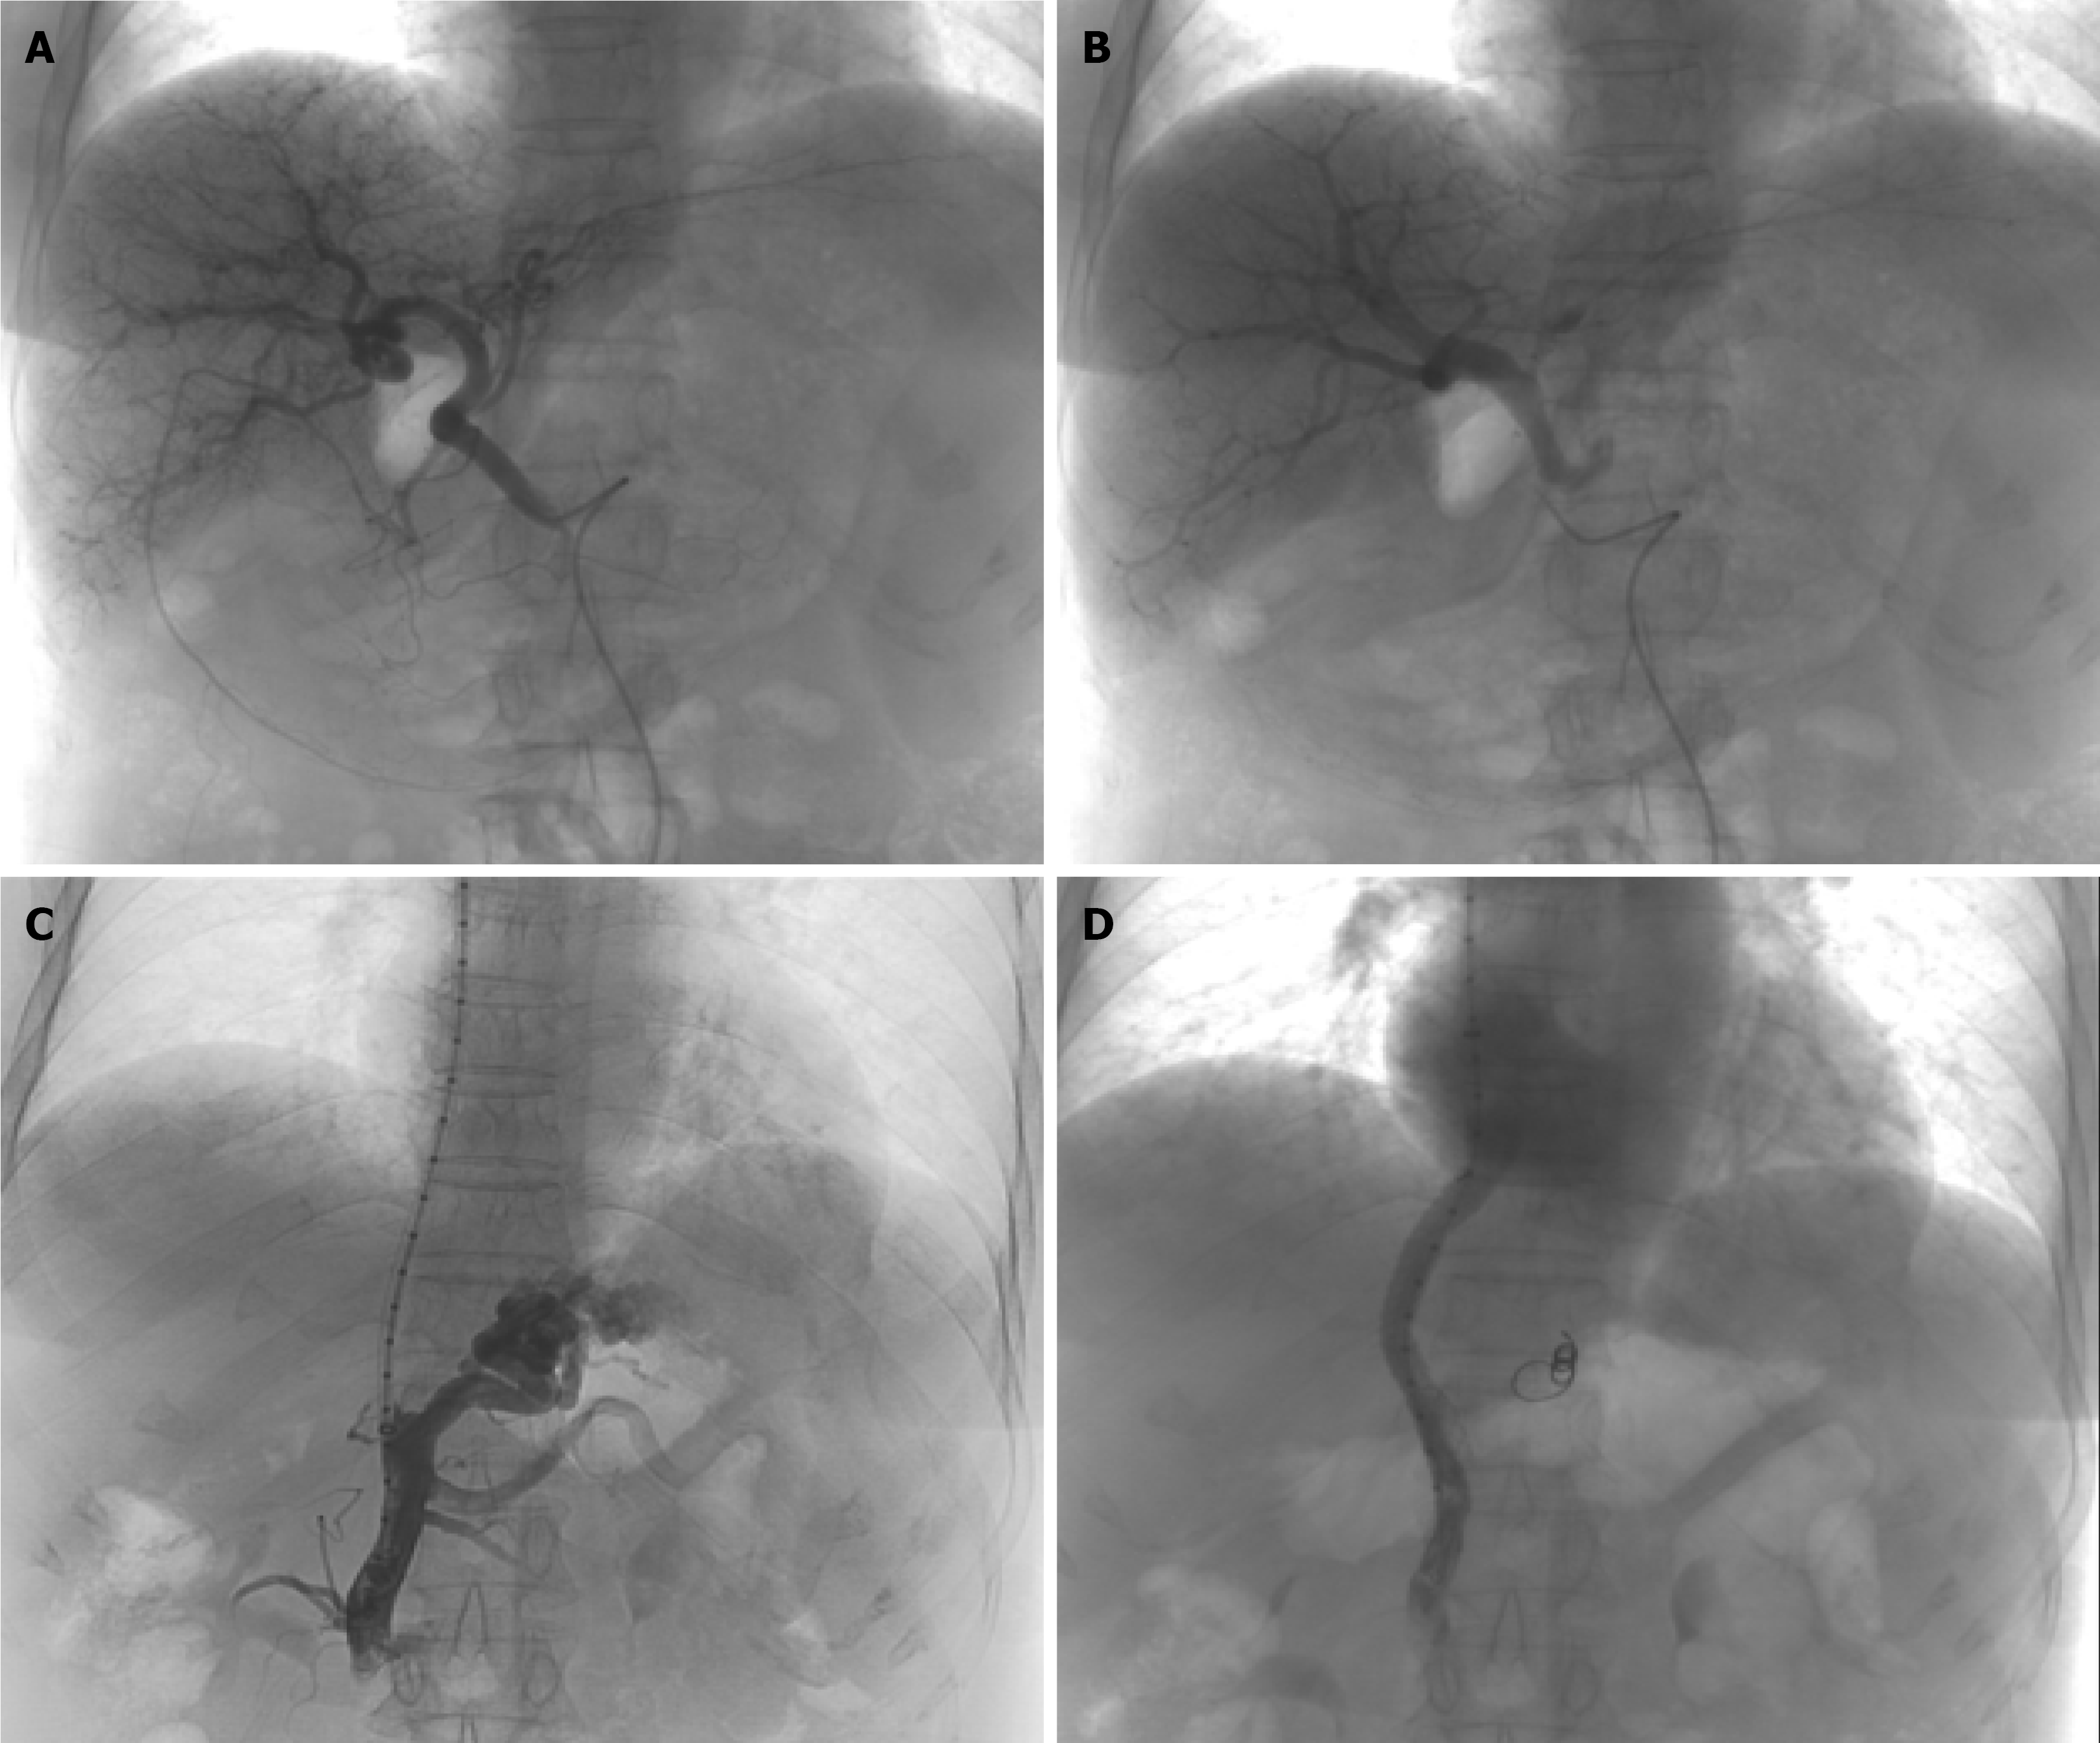

Variceal bleeding was therefore deemed secondary to both liver cirrhosis and high-flow arterioportal fistula. Then, the patient was treated with hepatic partial arterioportal fistula embolization under digital subtraction angiography (Figure 3A and B). However, melaena recurred two days post-operatively, suggesting persistent portal hypertension secondary to multiple fistulas even after embolization. Following comprehensive multidisciplinary evaluation and in